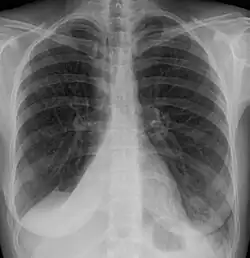

Atelectasis of the right lower lobe seen on chest X-ray.

Clinically significant atelectasis is generally visible on chest X-ray; findings can include lung opacification and/or loss of lung volume. Post-surgical atelectasis will be bibasal in pattern. Chest CT or bronchoscopy may be necessary if the cause of atelectasis is not clinically apparent. Direct signs of atelectasis include displacement of interlobar fissures and mobile structures within the thorax, overinflation of the unaffected ipsilateral lobe or contralateral lung, and opacification of the collapsed lobe. In addition to clinically significant findings on chest X-rays, patients may present with indirect signs and symptoms such as elevation of the diaphragm, shifting of the trachea, heart and mediastinum; displacement of the hilus and shifting granulomas.[13]